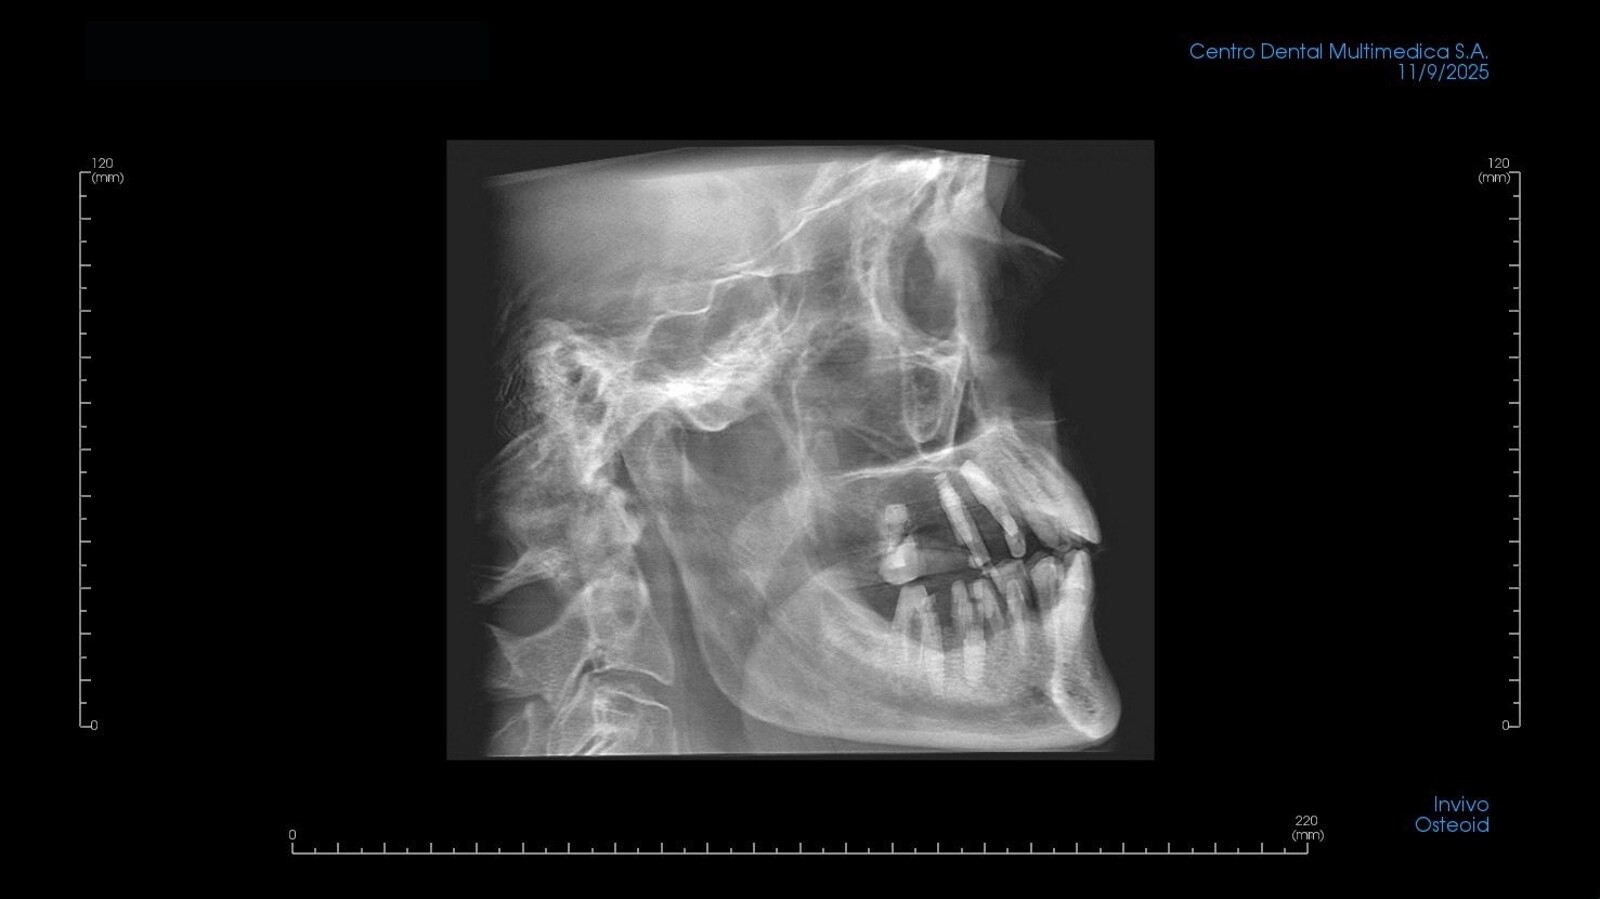

Radiografía lateral de cráneo de una reconstrucción con grafeno.